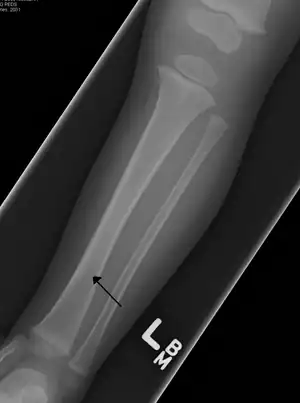

The initial radiographical images may be inconspicuous (a faint oblique line) and often even completely normal.[6] After 1–2 weeks however, callus formation develops.

The condition can be mistaken for osteomyelitis, transient synovitis or even child abuse. Contrary to CAST fractures, non-accidental injury typically affect the upper two-thirds or midshaft of the tibia.

Other possible fractures in this area, occurring in the cuboid, calcaneus, and fibula, can be associated or can be mistaken for a toddler's fracture.[8] In some cases, an internal oblique radiography and radionuclide imaging can add information to anterior-posterior and lateral views.[9][10] However, since treatment can also be initiated in the absence of abnormalities, this appears to have little value in most cases. It could be useful in special cases such as children with fever, those without a clear trauma or those in which the diagnosis remains unclear.[6][11] Ultrasound has also been suggested as a helpful diagnostic tool.[12]

Accidental or innocent toddler fracture/lateral